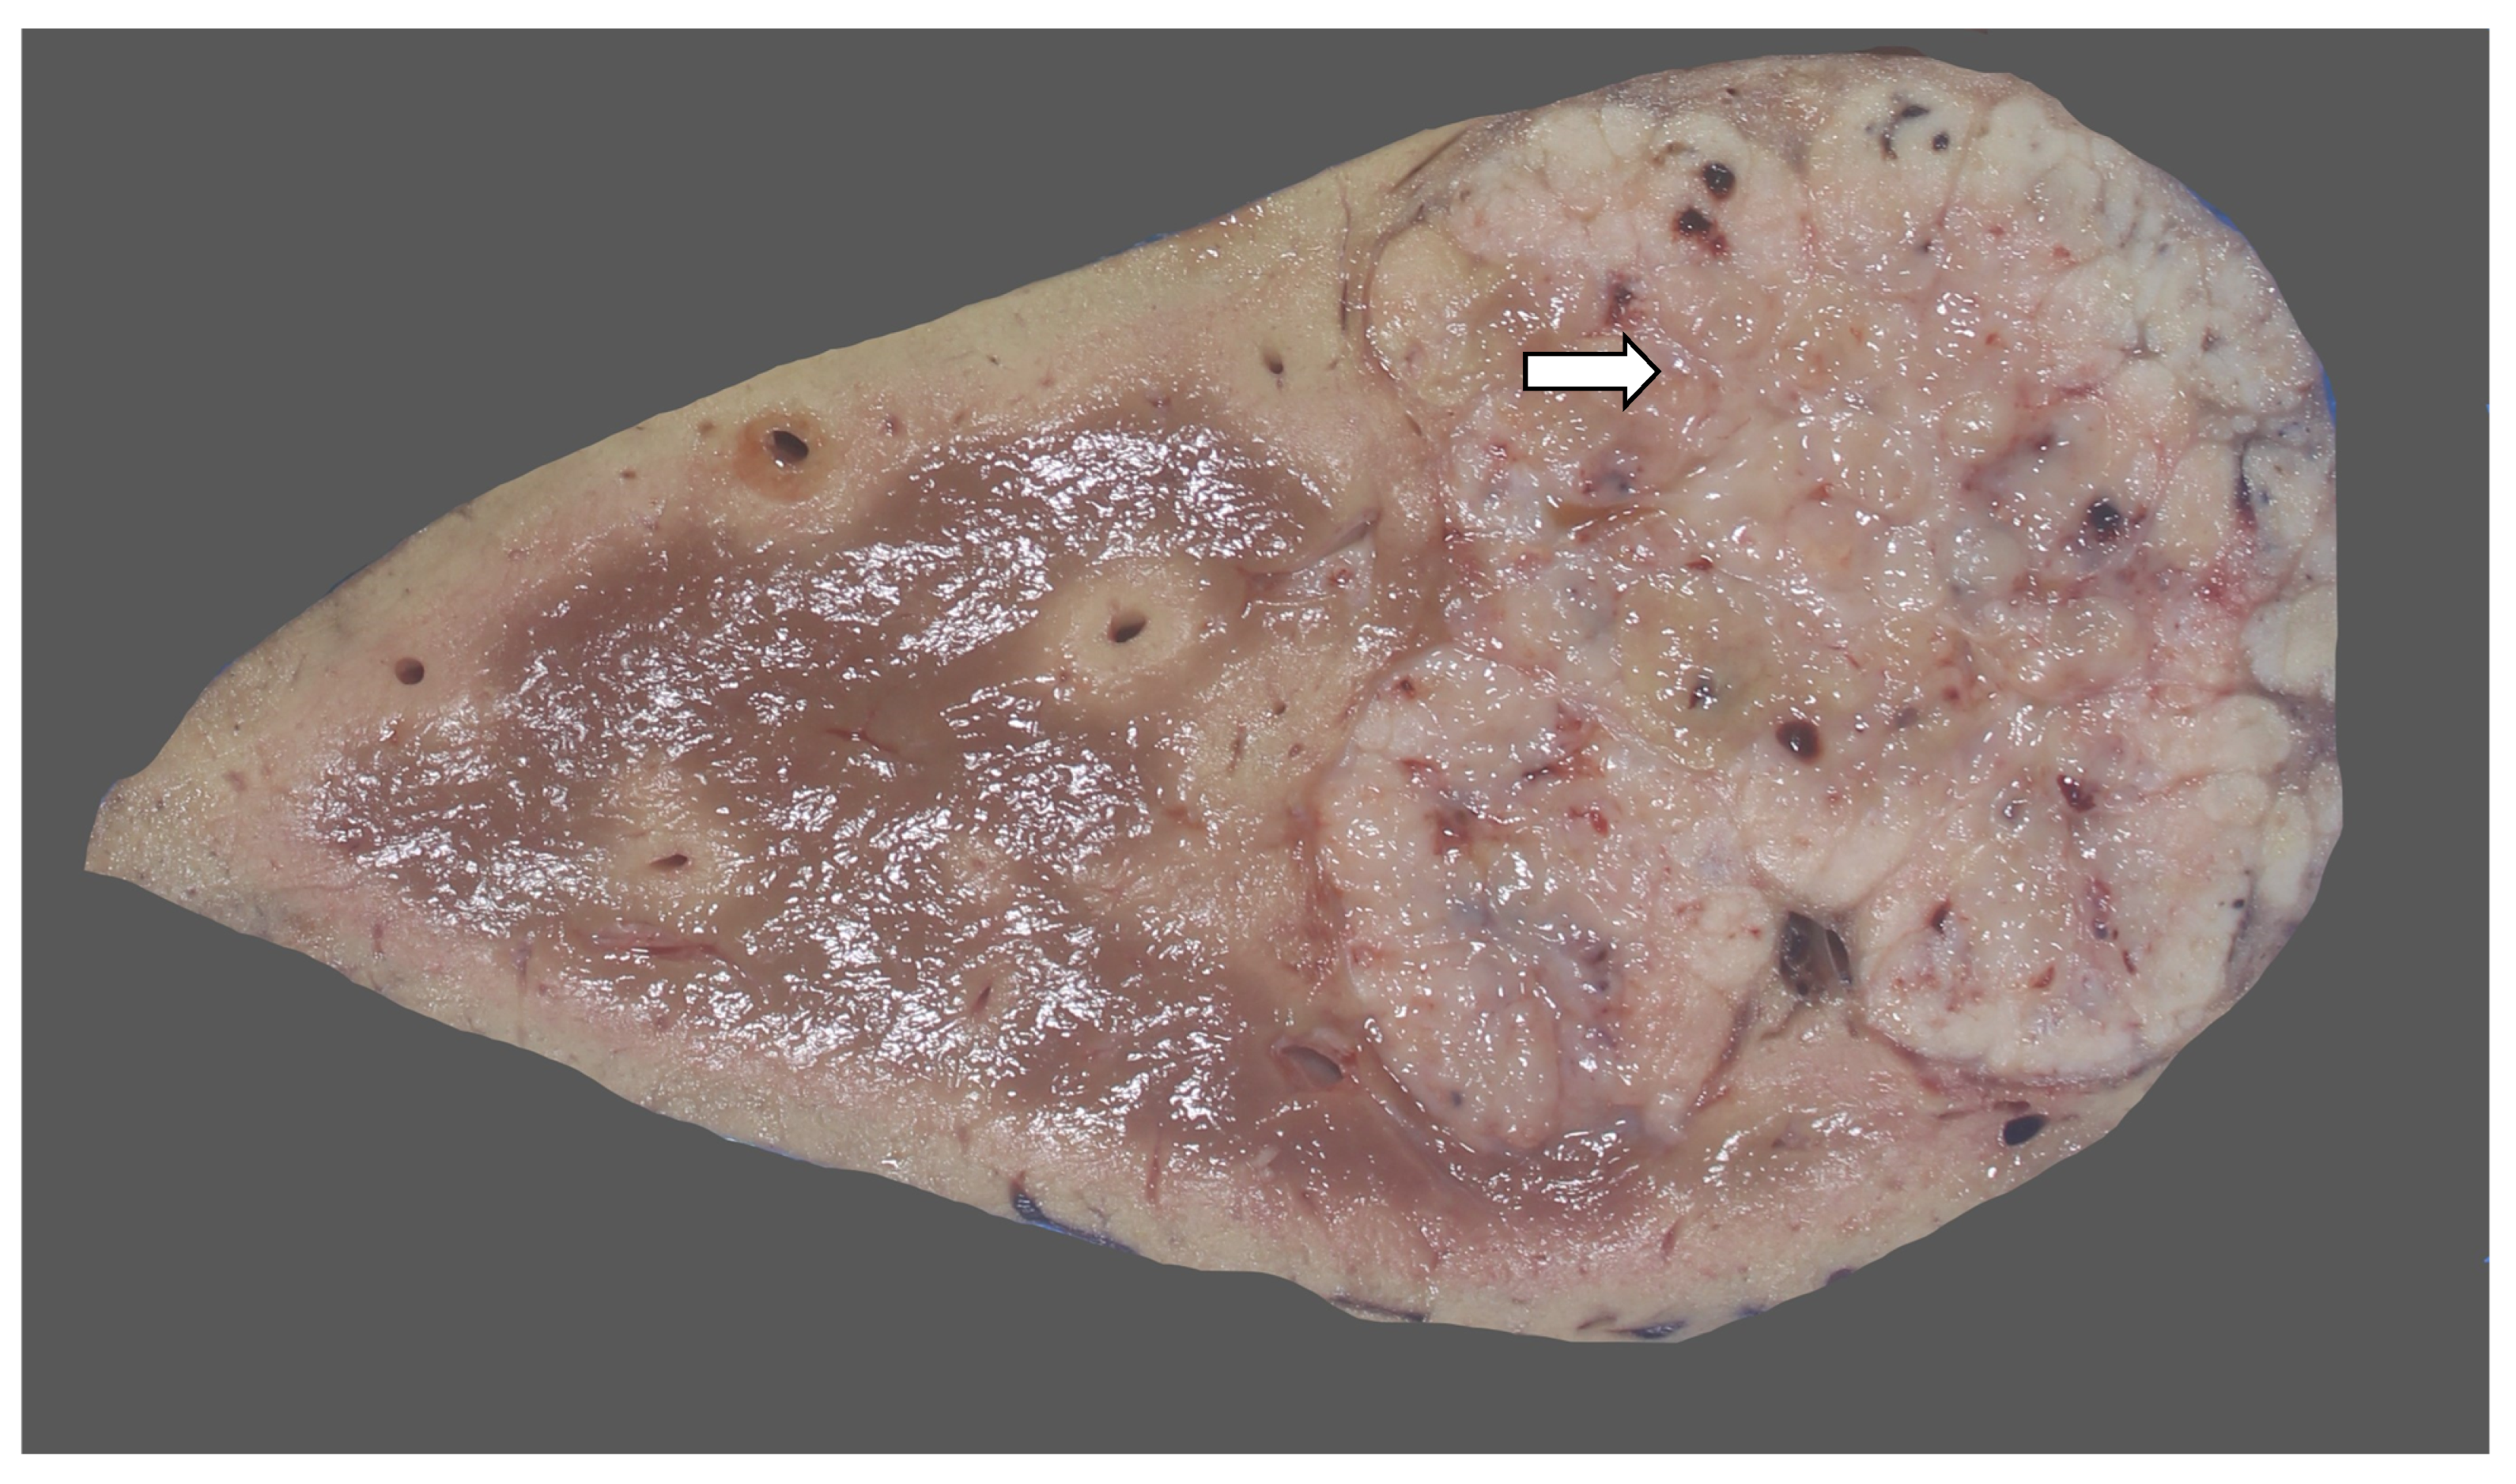

15. Hepatoblastoma

15.1. Clinical Presentation

15.2. Imaging Findings

15.3. Pathology